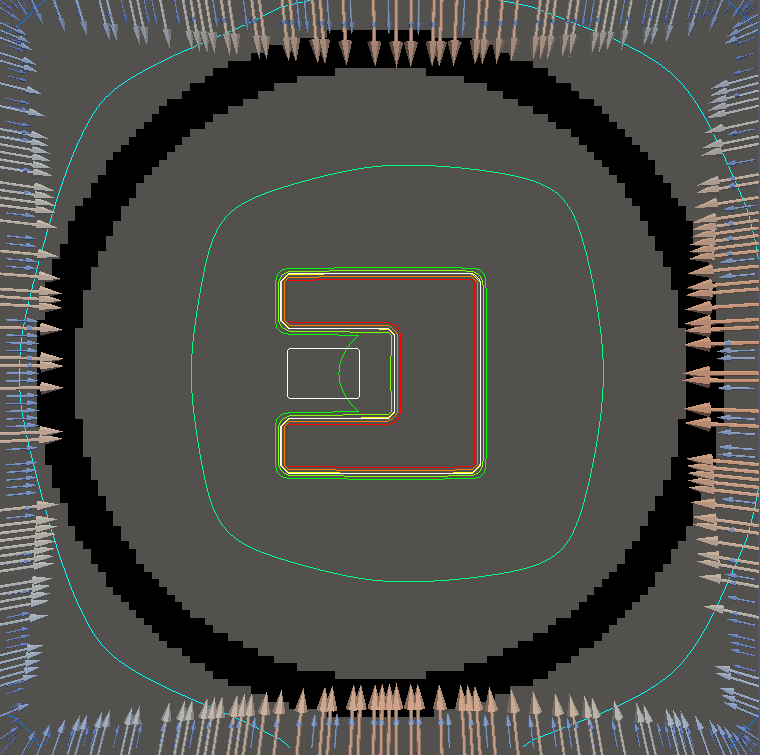

For testing, we use three tumor/risk region regions similar to those in [13]. Specifically, we define the regions in Table 3 and are shown in Figure 1; the void region is shown in black and the tumor and risk regions are traced in white. In the basic target case, seen in Figure 1(a), the tumor region is a box, as is the risk region. The second, intermediate target case, seen in Figure 1(b), involves an L-shaped tumor around a box-shaped risk region. Finally, the complex target case in Figure 1(c) involves a C-shaped tumor around a risk region.

Figure 2 shows the optimal boundary source term for both and The vectors shown on the boundary are the time-integrated values of normalized and then scaled by In Figures 2(a), 2(c), and 2(e) (corresponding to ), the isolines are spaced at intervals of the maximum of the desired dose (here, 5). In the intermediate and tracking cases, we see that relatively low dose levels are attained, primarily due to the high penalty to any dose deposited in the risk region. In Figures 2(b), 2(d), and 2(f)(corresponding to ), the isolines are spaced at intervals of of cells killed. Here a high proportion of the tumor cells are killed (in each case ) while in the Intermediate and Basic cases, the tumor has at least survival; in the Complex case, the risk region has survival.